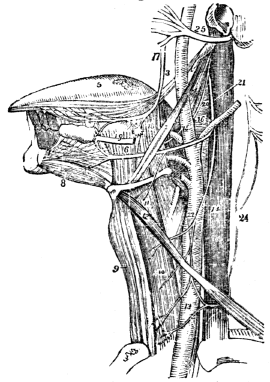

| 29. | Anatomy of the Vocal Organs, | 268 |

| 29. | Physiology of the Vocal Organs, | 272 |

| 30. | Hygiene of the Vocal Organs, | 274 |